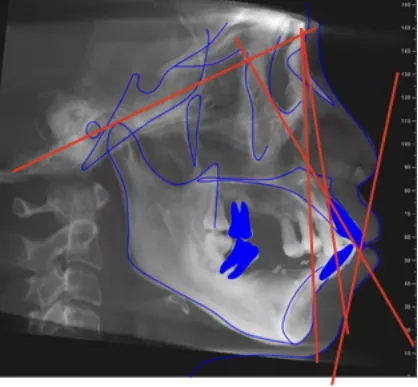

· 头影测量分析,临床诊断为:上颌前突,骨性二类错合畸形,上下中切牙及上下唇前突。

· 侧貌美学预告后,确定了上前牙矢状面前后向的位置关系,中切牙在矢状面上的位置变化:将唇倾的上前牙直立,上中切牙角度减小12度,切端内收8mm。

· 根据正侧貌美学预告,确定了咬合重建最重要的起点,上中切牙三维位置 ,𬌗面参看(FH平面)眶耳平面,并指导全口数字化排牙。